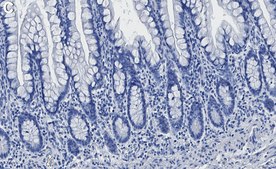

Immunohistochemistry (Paraffin) Analysis: A 1:100 dilution from a representative lot detected Vitamin D3 Receptor in Human small intestine tissue sections.